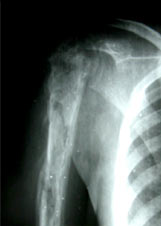

Koch's elbow